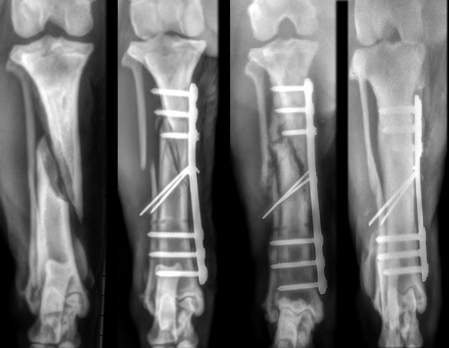

L’utilizzo di Placche e Viti

La riduzione con placca e viti, è un’ opzione chirurgica che viene utilizzata ampiamente (quando non siamo di fronte a traumi gravi) perchè presenta alcuni vantaggi:

– Riduzione anatomica dei frammenti soprattutto nelle fratture che interessano la superficie articolare.

– Precoce mobilizzazione dell’arto con riduzione del rischio di rigidità dell’articolazione.

![]() |

|

Placche e viti utilizzate nell’uomo |

Riduzione di una frattura con l’utilizzo di Placche e Viti nel Cane |